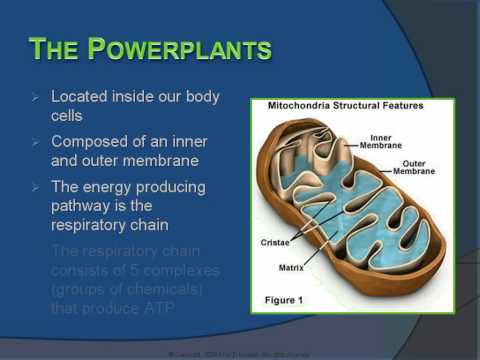

Mitochondria ATP and cellular respirtaion synthesis. Video streamed by www.AllthingsScience.com All [...]

8 minutes of a 40 minute presentation of basic background on Mitochondrial Disease and on its associ [...]